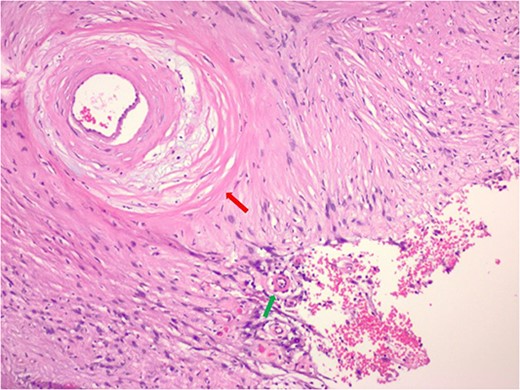

Hematoxylin and eosin stain pathologic slide of ancient schwannoma showing hyalinizing vessel (green arrow) and cystic degeneration (red arrow) characteristic of ancient changes.

Hematoxylin and eosin stain pathologic slide of ancient schwannoma (green arrow) and adjacent ganglioneuroma (red arrow) with ganglion cell (yellow arrow).